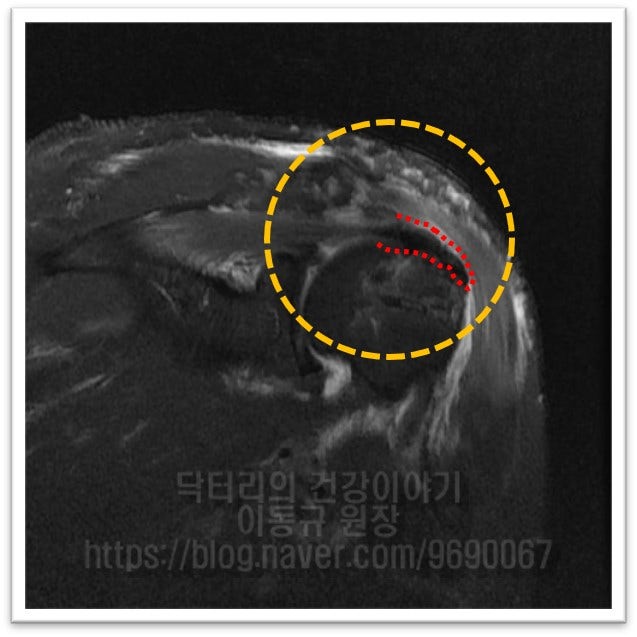

수술 후 MRI 를 비교해 보겠습니다.

중파열 정도로 보이며 관절경을 통한 회전근개 봉합술을 시행하였습니다.